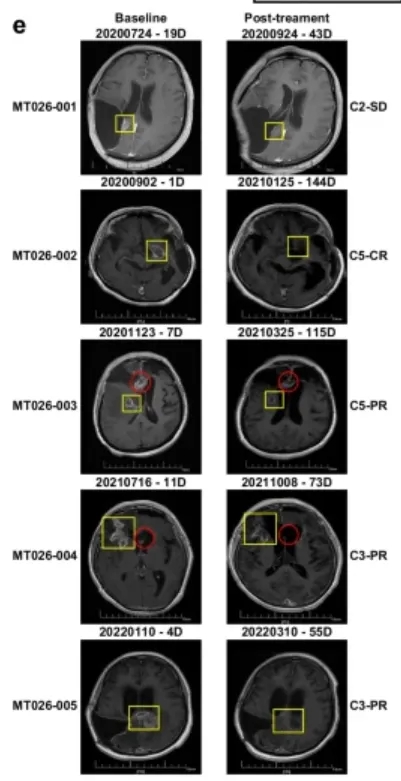

这项首次人体I期临床试验(试验编号:ChiCTR2000028801),共纳入5名复发高级别胶质瘤患者,这些患者均经过手术、放疗、替莫唑胺化疗等常规治疗失败,且病情危重,所有患者均为IDH野生型、MGMT启动子未甲基化(这两种都是预后极差的标志)。

就是这样一群被判定“预后极差”的患者,在接受MT026鞘内注射治疗后,交出了令人震撼的答卷:

客观缓解率80%:5名患者中,1名实现完全缓解(肿瘤完全消失),3名实现部分缓解(肿瘤明显缩小),1名病情稳定,没有1名患者出现病情进展,疾病控制率100%;

生存期大幅延长:从复发时间开始计算,患者的中位生存期达到13.1个月,12个月生存率80%,其中一名63岁的女性患者(MT026-002),复发后生存期更是达到了33.2个月,远超复发后6-8个月的中位生存期;

安全性极佳:所有治疗相关的不良事件均为1-2级,主要是发热、低氧血症、呕吐等轻微症状,均可自行缓解或经简单治疗后缓解,未出现任何3级及以上不良事件,也没有出现免疫效应细胞相关神经毒性综合征(ICANS)、感染等严重并发症。